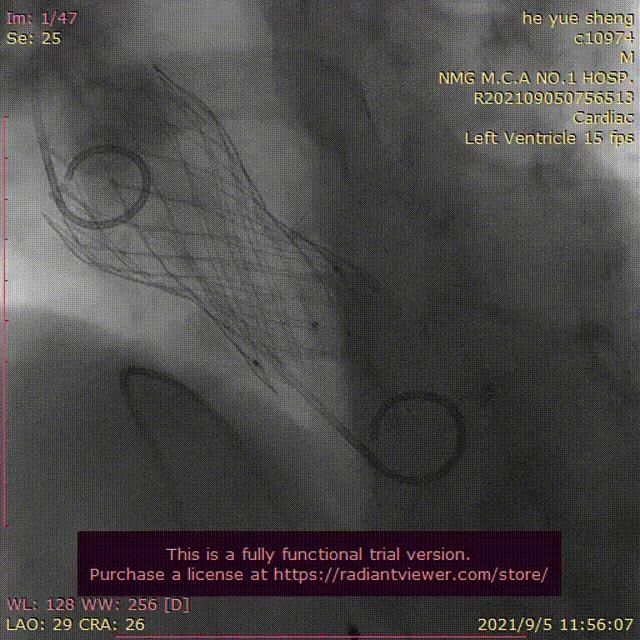

手术从患者大腿根处穿刺进入股动脉,送入导丝建立轨道,先于冠脉左前降支(LAD)中段、右冠脉狭窄段成功植入支架(PCI)。选用22mm球囊进行预扩张,在临时起搏器起搏下,再小心翼翼地将人工主动脉瓣膜通过导丝轨道,精准输送到预定位置,造影后无瓣周漏,手术顺利完成,术后患者心功能改善,好转出院。

文章插图

图由心脏大血管外科提供